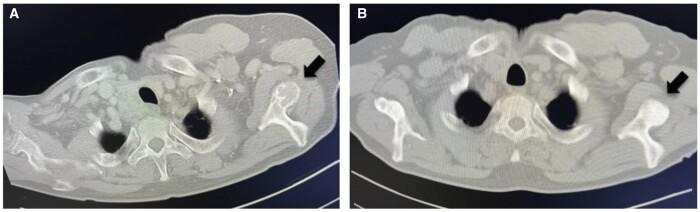

We present two rare cases of parathyroid carcinomas associated with multiple brown tumours. Plain radiographs, computed tomography, and neck ultrasonography revealed the presence of bone and parathyroid tumours. Despite the use of 99m Tc-methoxy isobutyl isonitrile (99mTc-MIBI) or F-fluorodeoxyglucose-positron emission tomography (18F-FDG PET)/CT, it was difficult to differentiate bone metastases from brown tumours. Parathyroid carcinoma was confirmed by histopathological examination following parathyroidectomy, resulting in spontaneous bone lesion improvement. In patients with parathyroid carcinoma presenting with bone lesions suggestive of metastasis, understanding the potential for brown tumour accumulation through 99mTc-MIBI or 18F-FDG PET/CT is pivotal. With this understanding, it is possible to diagnose brown tumours with parathyroidectomy and follow up for improvement of bone lesion and avoid invasive biopsy or surgery.

我们报告两例罕见的与多发性棕色瘤相关的甲状旁腺癌病例。X线平片、计算机断层扫描和颈部超声检查发现存在骨骼和甲状旁腺肿瘤。尽管使用了99m锝-甲氧基异丁基异腈(99mTc-MIBI)或氟-氟脱氧葡萄糖-正电子发射断层扫描(18F-FDG PET)/CT,但很难区分骨转移瘤和棕色瘤。甲状旁腺癌经甲状旁腺切除术后的组织病理学检查得以确诊,随后骨骼病变自发改善。对于表现出提示转移的骨病变的甲状旁腺癌患者,通过99mTc-MIBI或18F-FDG PET/CT了解棕色瘤积聚的可能性至关重要。有了这种认识,就有可能通过甲状旁腺切除术诊断棕色瘤,并对骨病变的改善情况进行随访,避免进行侵入性活检或手术。